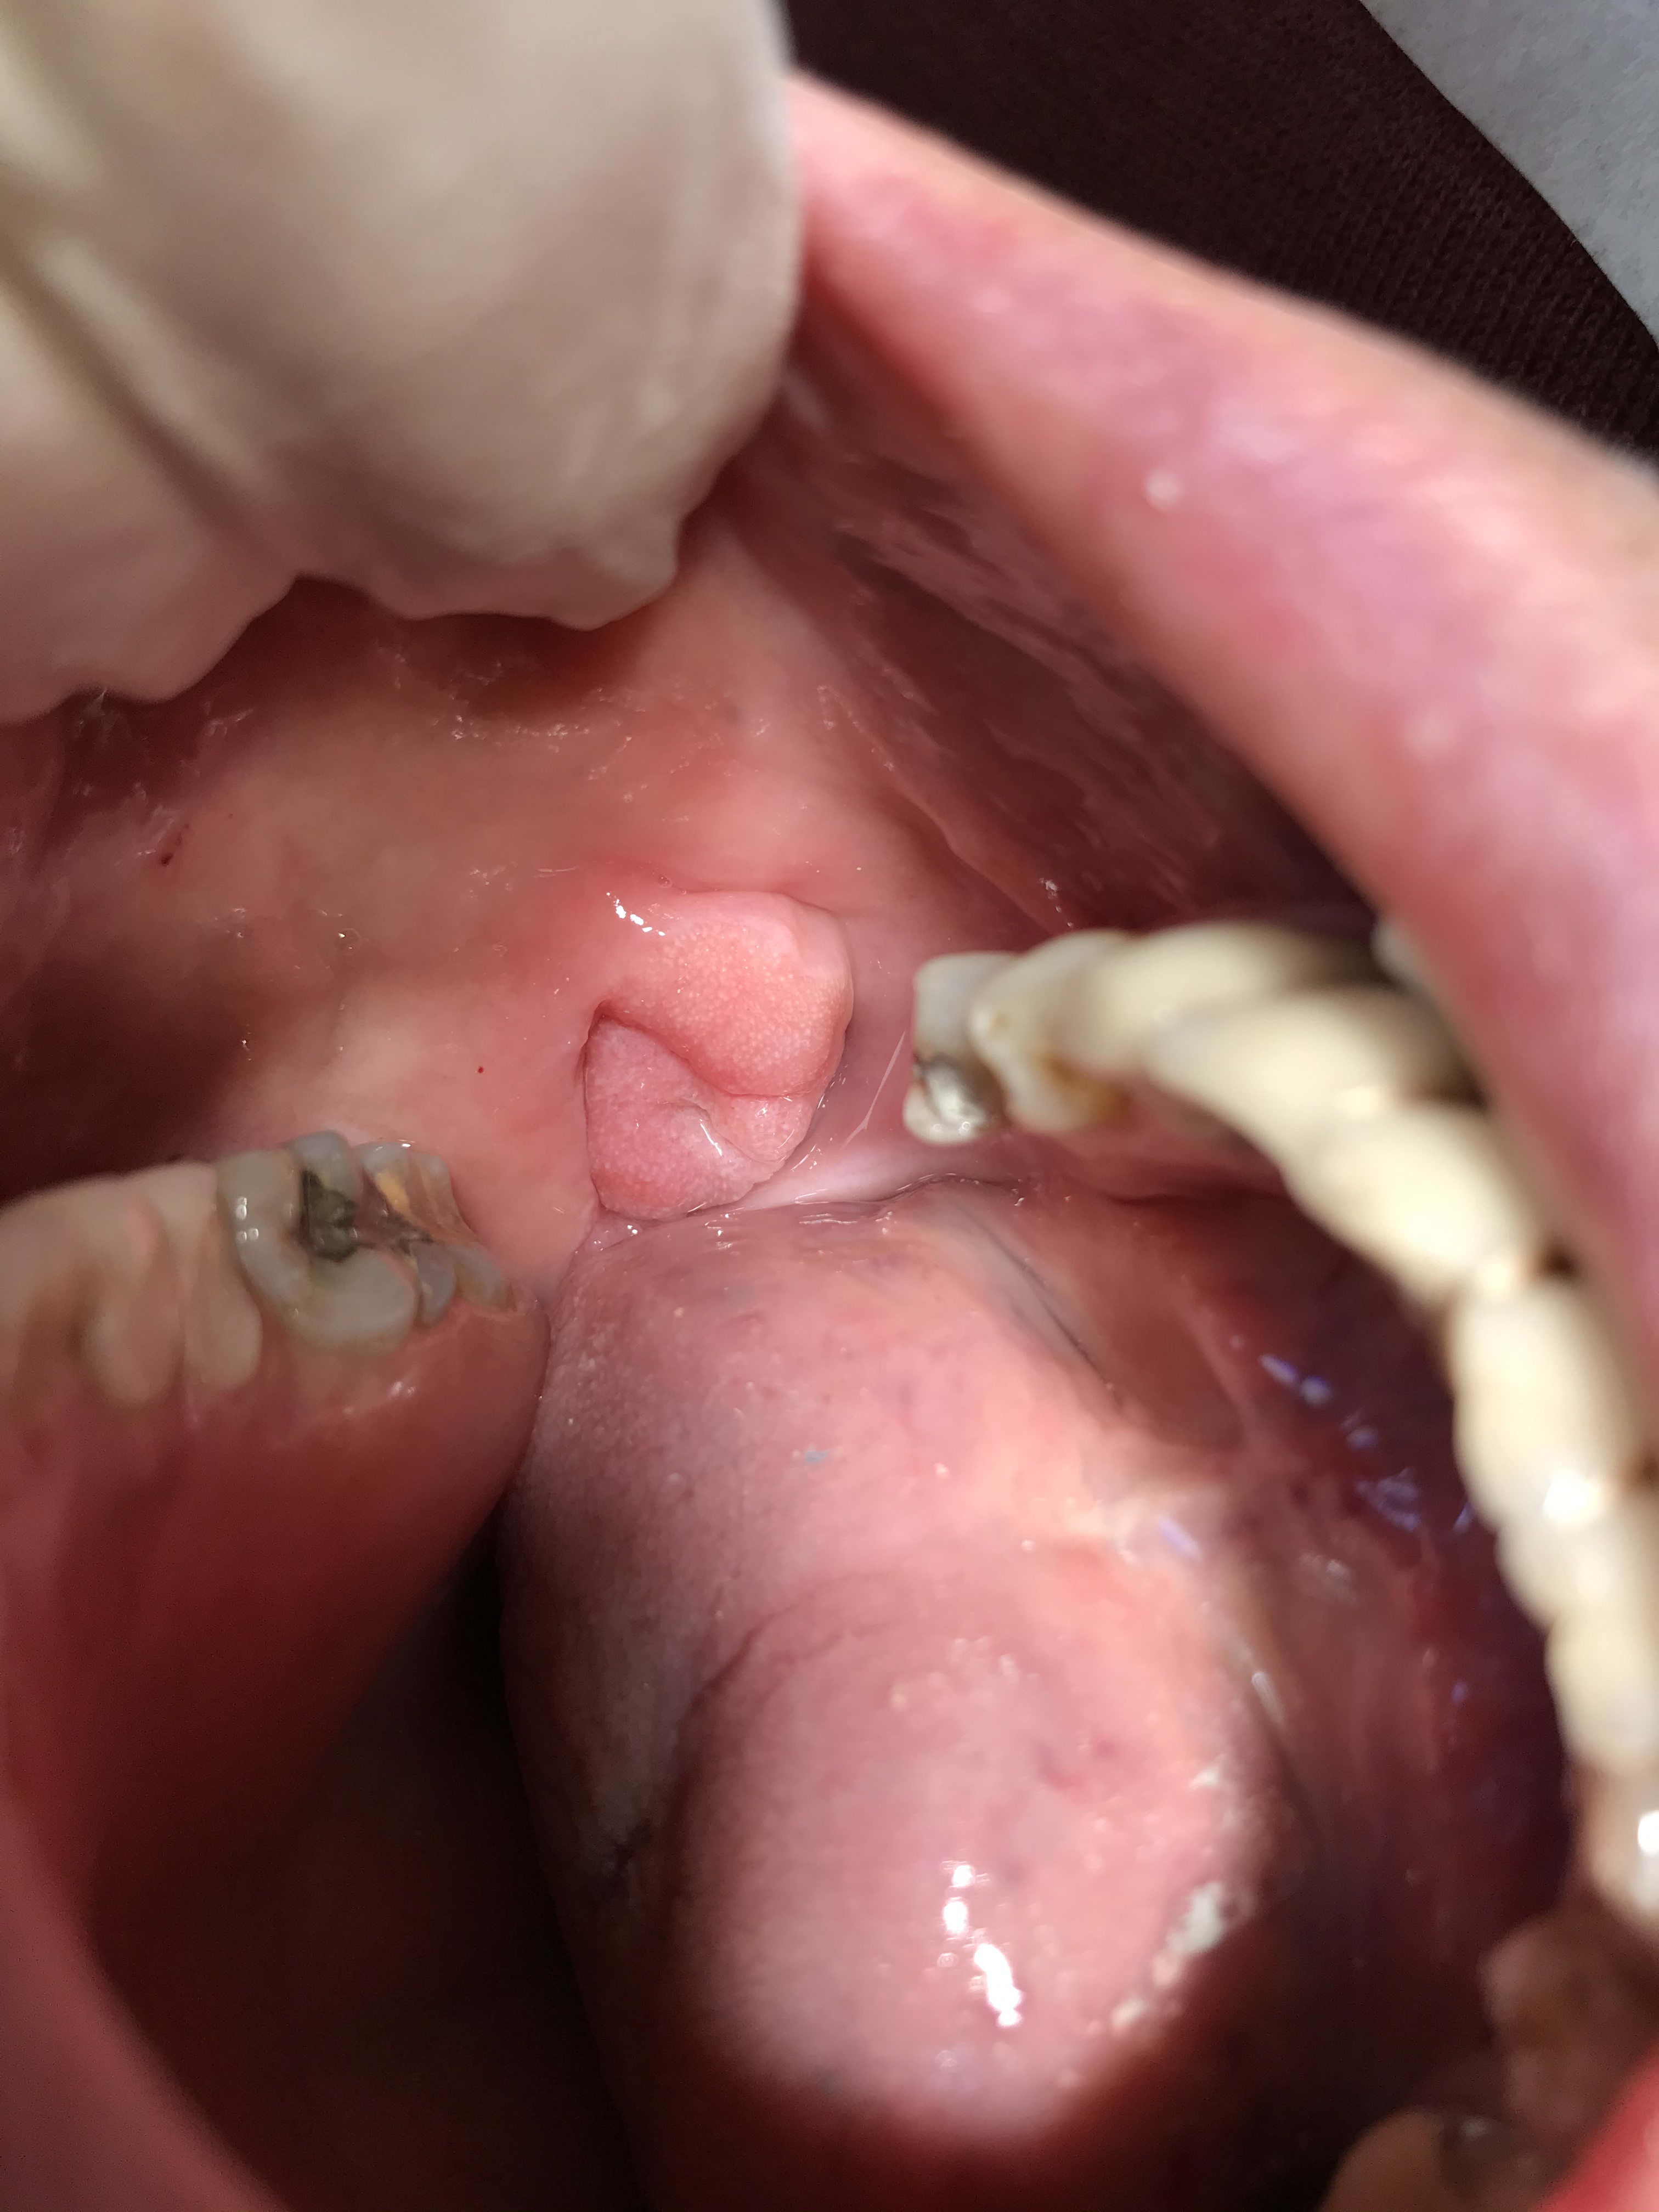

Regarde moi ça Vulpi , celui-ci je lui ai mis 7 implants qui sont en train de prendre au maxillaire, je lui fais un bridge à droite pour l’occlusion. Et à gauche il a une grosse boule semi molle qui est apparue sur la face interne de la joue. Il ne veut pas que je lui case une 36 sur implant ...

C’est quoi ça ? Juste une hypertrophie gingivale en regard des dents manquantes ? Tu découpes ça comme une tranche de jambon ... ?

J'adresse, j'aime pas le sang 😁

Mais si tu bouches pas le trou, ça risque de récidiver.